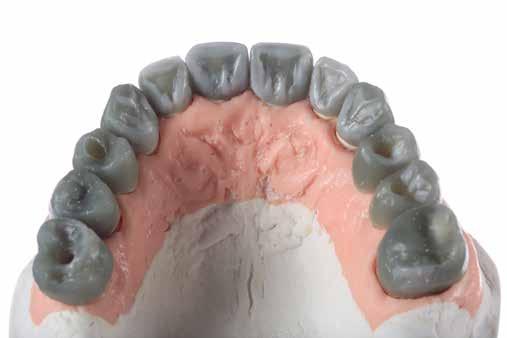

A tesztprojektünk megerősítette, hogy a KATANA Zirconia

potenciállal rendelkezik, és az indikációs területe határtalan.

pozicionálása a virtuális nyersdarabban, marás után pedig az illeszkedés

Zirconia YML kiváló minőségű anyag, amely nagy esztétikai határtalan. Meglepően egyszerű a restaurációk tervezése és pedig a felületek simák, a szélek élesek és határozottak, pedig pontos.

Amikor a fogászati cirkónium rendkívül esztétikus anyaggá fejlődött alkalmassá válva a monolitikus kialakítású vagy minimális labiális visszavágású pótlások készítésére, a kézzel végzett munka (kerámia rétegezés) mennyisége csökkent. Ugyanakkor minden fogtechnikai laboratóriumnak több elérhető nyersdarabra volt szüksége, és az indikáció-specifikus anyag -

választás igénye bonyolította a tervezési folyamatokat.

Egyes fogtechnikusok előszeretettel játszanak a különböző korongokkal és az automatizált és kézi munkafolyamatok kombinációjával, hogy pontosan megfeleljenek a páciens és az indikáció-specifikus igényeknek. Mások azonban egy gyorsabb és szabványosabb utat választanának